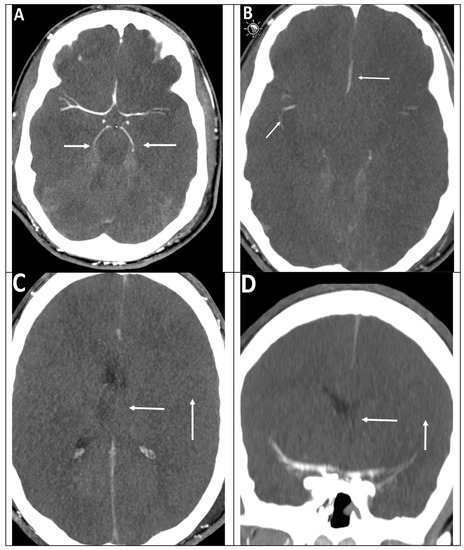

Example of BRAINDEXweb-Workflow in the Context with False-Negative CTA-Signs Caused by Decreased Intracranial Pressure (ICP) in Suspected BD